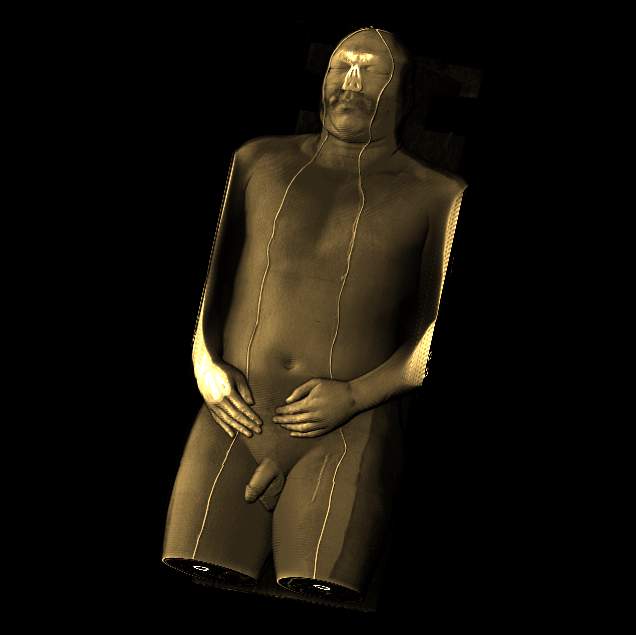

Visible human male CT data

Shaded whole

body with skin

Data Resolution : 512x512x1294